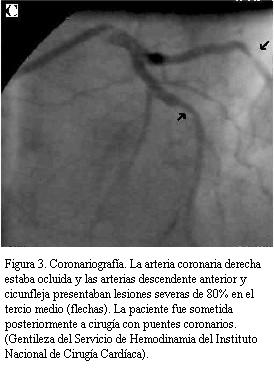

Todos salvo un paciente (portador de BCRI) tenían en el electrocardiograma basal alteraciones de la repolarización compatibles con isquemia subendocárdica, con desniveles de 1 a 4 mm del segmento ST y scores totales entre 1,12 a 3,0 (promedio 2,05). Después de aplicar los fármacos, las alteraciones de la repolarización mejoraron o se normalizaron en 13 pacientes (86%) y se obtuvieron scores segmentarios entre 1,06 y 2,56 (promedio 1,50) con mejorías entre 10% y 40% (figuras 1, 2 y 3).

Doce de los 16 pacientes (75%) fueron estudiados con cateterismo a posteriori (promedio 12 días; rango de 0 a 72 días) y en diez de ellos (83%) se encontraron lesiones coronarias severas.

Siete de los ocho pacientes que no tenían antecedentes de cardiopatía isquémica presentaban lesiones severas (cinco con lesiones de tres vasos, uno de ellos además tenía lesión de tronco, uno con lesión de dos vasos y un paciente con lesión de un vaso).